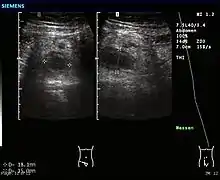

Ultrasound image of acute appendicitis

Abdominal ultrasonography, preferably with doppler sonography, is useful to detect appendicitis, especially in children. Ultrasound can show the free fluid collection in the right iliac fossa, along with a visible appendix with increased blood flow when using color Doppler, and noncompressibility of the appendix, as it is essentially walled-off abscess. Other secondary sonographic signs of acute appendicitis include the presence of echogenic mesenteric fat surrounding the appendix and the acoustic shadowing of an appendicolith.[45] In some cases (approximately 5%),[46] ultrasonography of the iliac fossa does not reveal any abnormalities despite the presence of appendicitis. This false-negative finding is especially true of early appendicitis before the appendix has become significantly distended. Also, false-negative findings are more common in adults where larger amounts of fat and bowel gas make visualizing the appendix technically difficult. Despite these limitations, sonographic imaging with experienced hands can often distinguish between appendicitis and other diseases with similar symptoms. Some of these conditions include inflammation of lymph nodes near the appendix or pain originating from other pelvic organs such as the ovaries or Fallopian tubes. Ultrasounds may be either done by the radiology department or by the emergency physician.[47]